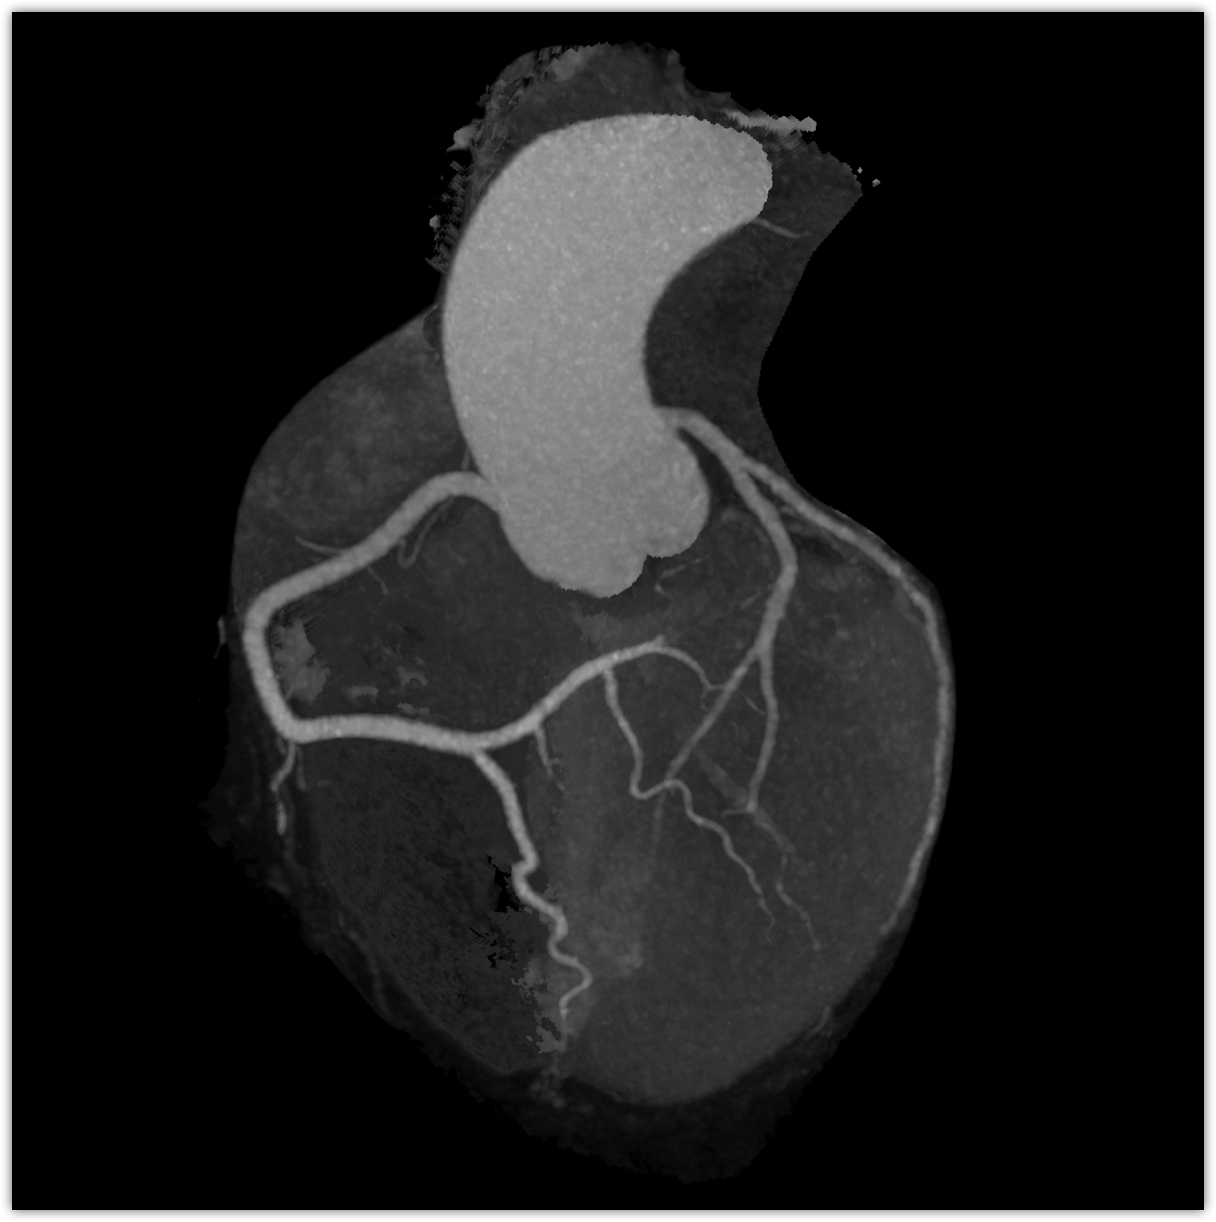

We believe in keeping you as healthy as possible. One of the ways we do this is by checking for heart disease with a Coronary CT Angiogram (CCTA) — a non-invasive scan that can see disease in your heart vessels even if you have no symptoms.

Most people have no symptoms until it’s too late. A Coronary CT Angiogram (CCTA) lets us see disease in the vessels of your heart — before a heart attack happens.

LAD scan